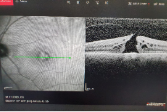

Makula deliği şikayetleri ile başvuran hastada ilk önce yapmamız gereken hastanın görme keskinliğine bakıp ayrıntılı reina muayenesi yapmaktir. Eğer delikten şüphelenirsek teşhiste altın standart ve %100 tanı koydurucu tek test OCT dir. OCT ağrısız ve boyasız noninvaziv bir yöntem olup hastalığın teşhisınde tek yöntemdir.

Resim 1: Bu resimde kliniğimizdeki 70 yaşındaki bir bayan hastaya ait makula deliğinin OCT görüntüsü görülmektedir. Hastamızın görmesi %1 olup şikayetleri 3 aydan beri devam etmekteydi.